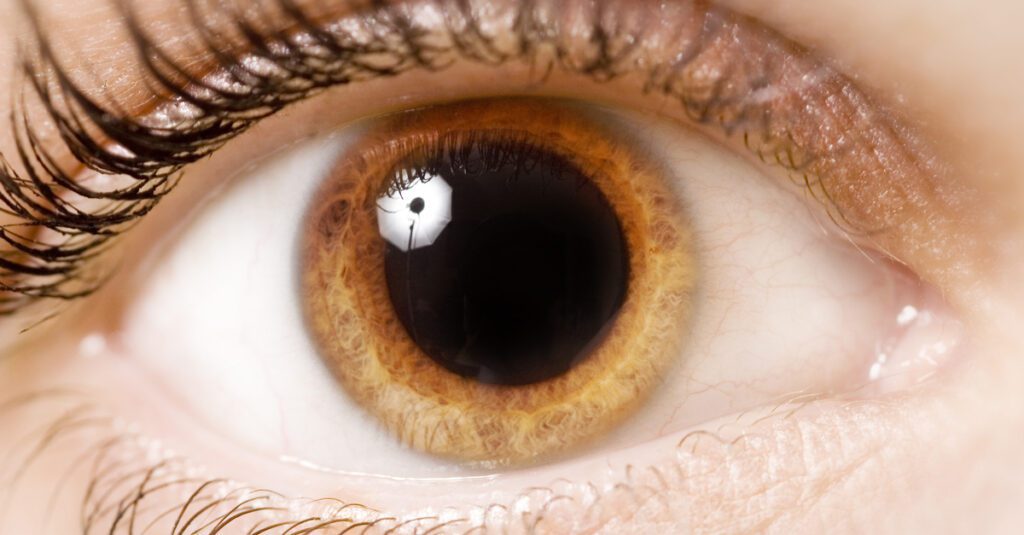

بؤبؤ العين و الأجراءات الجراحية المناسبة

ما هو البؤبؤ؟

بؤبؤ العين عبارة عن فتحات داكنة اللون في مركز عينيك تسمح بدخول الضوء. يمكن للأطباء أن ينظروا إلى بؤبؤك بحثًا عن أدلة حول صحتك.

يمكن أن يساعد حجم بؤبؤ العين وكيفية تفاعلهم مع الضوء في تشخيص بعض المشكلات الصحية. على سبيل المثال إذا تعرضت لضربة في الرأس وكان أحد بؤبؤك أو كلاهما متسعًا – أكبر من الطبيعي – فقد يكون ذلك علامة على إصابة دماغية خطيرة .

ما هو تقبض بؤبؤ العين؟

الدائرة السوداء في وسط عينك هي حدقة عينك. يتغير حجمه آلاف المرات في اليوم. عندما تكون في ضوء خافت يكبر للسماح بدخول المزيد من الضوء. وعندما تكون في ضوء ساطع يتقلص لحماية عينك وإبعاد الضوء.